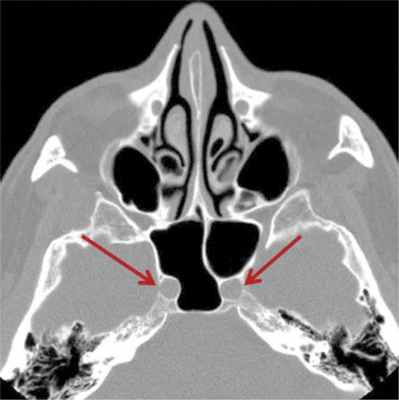

Фронтальный КТ срез через клиновидную пазуху.

Левая клиновидная кость сверху пневматизирована экстрамуральной решетчатой клеткой, снизу — клиновидной пазухой.

Поскольку в клиновидной пазухе не бывает горизонтальных перегородок, появление такой структуры подразумевает распространение решетчатых клеток в клиновидную кость.

Р ethm — Задние решетчатые клетки; SS — Клиновидная пазуха